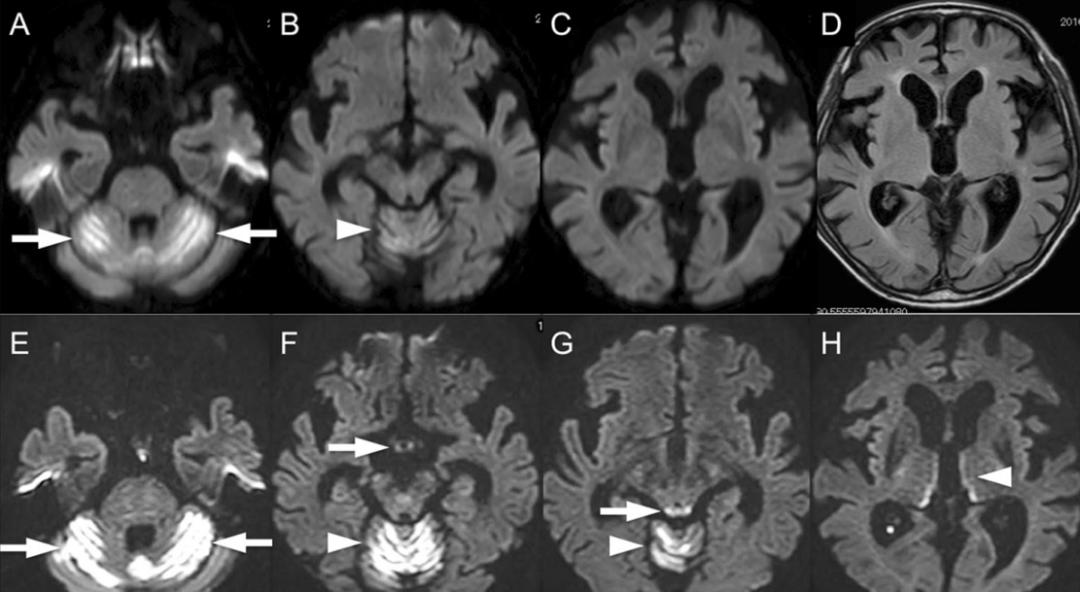

男,54歲,白血病病史。臨床表現(xiàn)為意識障礙、共濟失調。Flair示高信號位于雙側舌下神經(jīng)核(A)、前庭神經(jīng)內側核(B)、面神經(jīng)核(長箭頭)和展神經(jīng)核(短箭頭)(C)、中腦頂蓋和導水管周圍灰質(D)、乳頭體(E)、下丘腦和第三腦室周(F)。

男,73歲,多發(fā)性骨髓瘤化療后惡心、嘔吐1個月。臨床表現(xiàn)為小腦性共濟失調、眼肌麻痹、雙側水平眼震。顱腦DWI示:雙側小腦半球、蚓部彌散受限(A-C)。Flair未見第3腦室周異常信號。復查DWI示:除之前病灶灶(E),還可見雙側乳頭體(F)、中腦頂蓋(G)、丘腦內側(H)彌散受限。